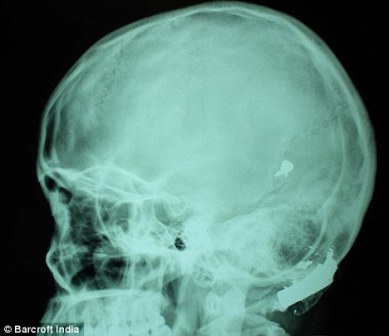

其中一顆子彈擊中她的左中耳,穿透了她的耳骨,然后擊中頭骨,嵌在了腦子里。另外兩顆子彈分別擊中她的右臂和心臟。印度Lok Nayak醫(yī)院的醫(yī)生稱,赫娜能夠康復完全是奇跡,她也足夠幸運。她的主治醫(yī)生稱:“當我們看到她的情況時,被嚇了一跳,幸運的是她活了下來!

這顆子彈沒有損壞大腦中控制身體機能的部分。盡管赫娜的手術很成功,但醫(yī)生表示,她還有出現(xiàn)感染和并發(fā)癥的可能。子彈毀掉了她的中耳,可能導致她耳聾。(楊柳)